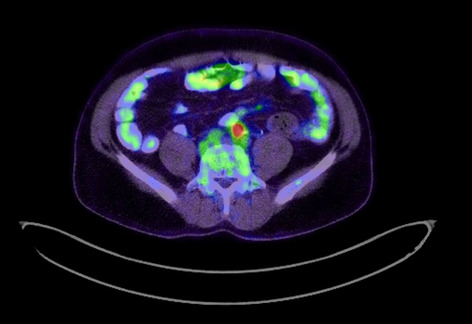

Colorectal—Malignant

O193—The role of 3D modelling technology in recognition of colorectal tumour deposits

Aims: 3D modelling technology is rapidly gaining interest in various fields of surgery. It can be used for operative planning and navigation, as well as surgical education and patient interaction. It allows for depiction of complex anatomical relationships in a more comprehensible way than traditional radiological images. However, it also has potential to become a tool facilitating gaining further understanding of surgical pathology by allowing to display and analyse imaging data in a new way. Tumour deposits are a challenging entity. They are currently being closely investigated with an aim to develop understanding of their role in colorectal cancer spread. It is an ever evolving concept which requires further research to fully appreciate the origin and significance of tumour deposits. We applied the novel 3D modelling technology to illustrate tumour deposits in colorectal cancer.

Methods: 3D virtual models were created through manual segmentation of CT and MRI scans obtained according to protocols routinely used in colorectal cancer staging. No extra patient time or preparation were needed. CT and MRI images were analysed by Gastrointestinal Radiologist to delineate the tumour and provide the cancer staging. Manual segmentation was then performed in 3D Slicer, an open-source, free software used for creation of three-dimensional anatomical models. Additional post-processing was applied in MeshLab or Blender.

Results: Ten 3D models depicting tumour deposits in colorectal cancer were created. Models of right- and left-sided bowel cancer with tumour deposits were derived from CT scans, while those of rectal cancer—from MRI scans. 3D models depicted bowel with the tumour and tumour deposits, relevant vasculature and lymph nodes, as well as surrounding structures as required. Models can be manipulated to allow for most comprehensible inspection of different anatomical structures and relationships. The transparency of each structure can be changed. The morphological appearance of tumour deposits and their relation to vessels can be readily appreciated. The morphological differences between the tumour deposits and lymph nodes, both benign and metastatic, can also be evaluated.

Conclusions: This work follows on from our previous experience with exploration of 3D modelling technology to map tumour deposits in rectal cancer, based on rectal MRI images. This innovative technology shows a huge potential to enhance our understanding of surgical pathology. It can provide a welcome assistance in exploring new concepts and developing new theories. It can facilitate communication and discussion around the evolving concepts. It is a versatile novel tool which can be successfully applied for depiction of tumour deposits in any part of the bowel. Here we showed its feasibility for the use in left- and right-sided bowel cancer, in addition to previously explored rectal cancer. It can utilise modalities commonly used in colorectal cancer staging – CT and MRI, which renders it clinically applicable. While there is an ongoing debate on the correct classification of tumour deposits and their full significance in metastatic process, as well as their prognostic value, 3D technology can facilitate familarisation with their appearance. It can also become an educational tool both for radiologists and surgeons and a valuable adjunct in the multidisciplinary management of colorectal cancer.